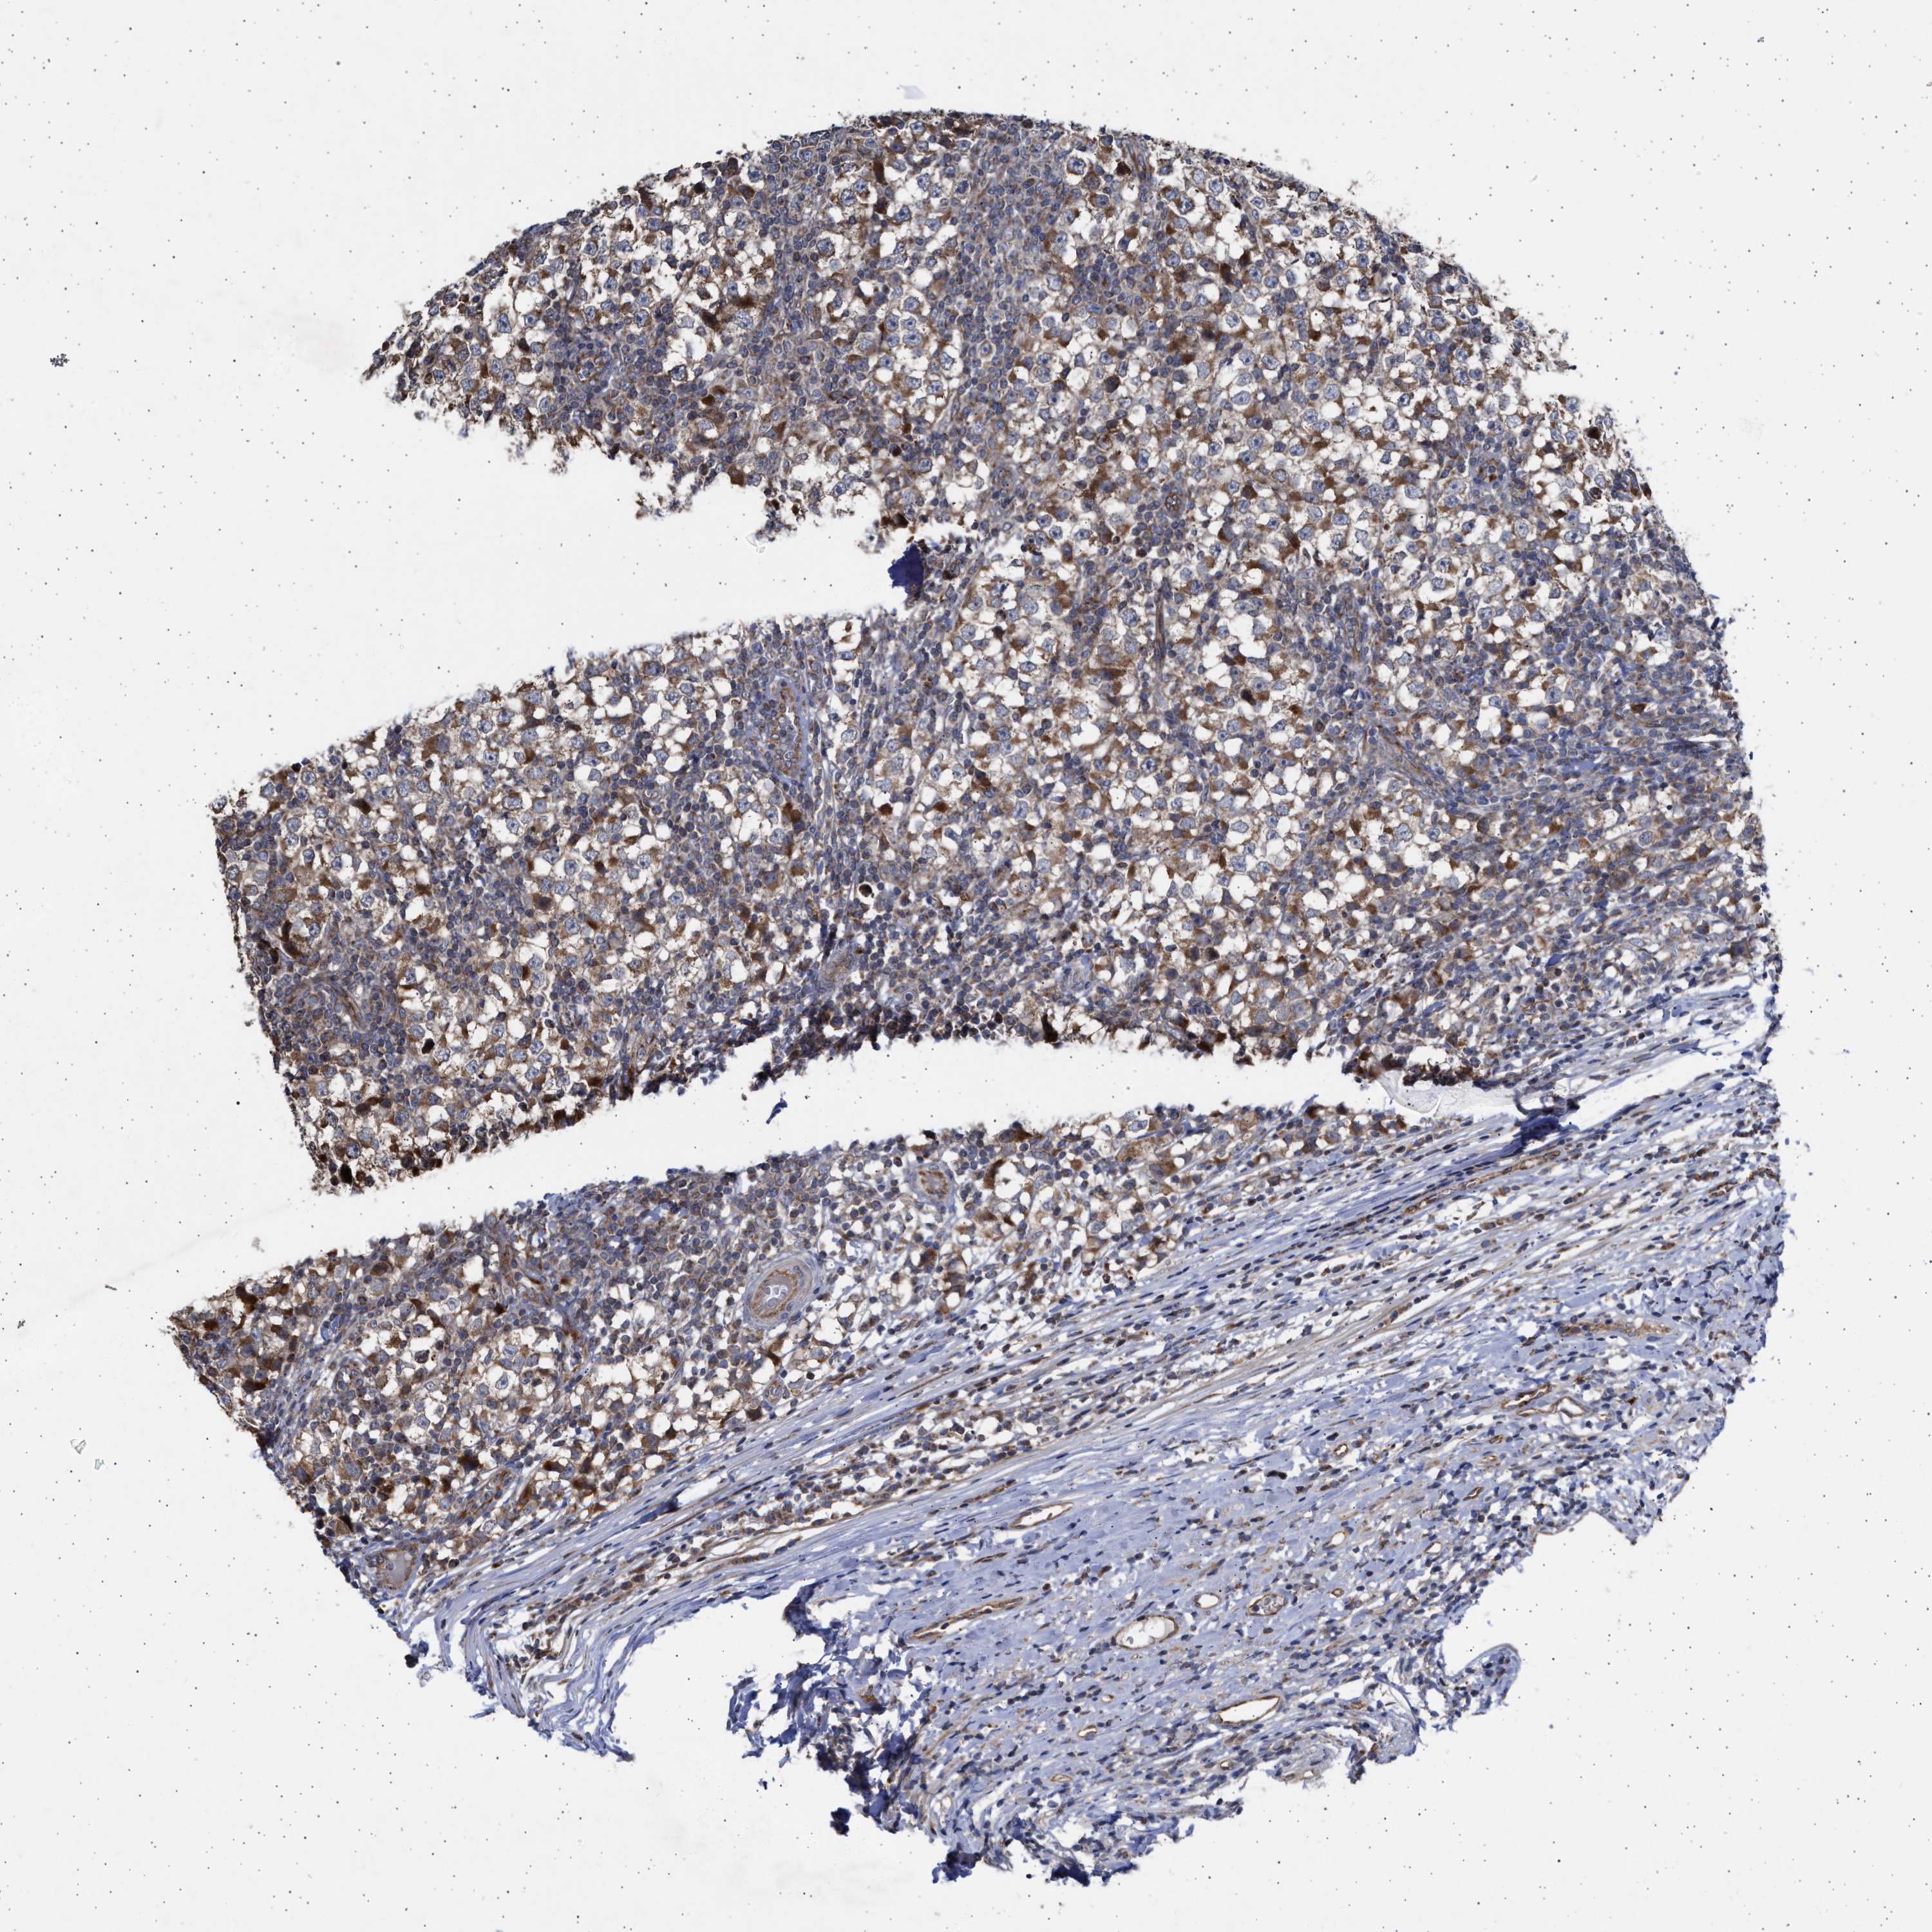

TESTIS CANCER - Protein expressioni

A mouse-over function shows sample information and annotation data. Click on an image to view it in a full screen mode. Samples can be filtered based on level of antibody staining by selecting one or several of the following categories: high, medium, low and not detected. The assay and annotation is described here.

Note that samples used for immunohistochemistry by the Human Protein Atlas do not correspond to samples in the TCGA dataset.

Antibody stainingi

Antibody staining in the annotated cell types in the current human tissue is reported as not detected, low, medium, or high, based on conventional immunohistochemistry profiling in selected tissues. This score is based on the combination of the staining intensity and fraction of stained cells.

Each image is clickable and will lead to virtual microscopy that enables deeper exploration of all samples and also displays staining intensity scores, fraction scores and subcellular localization as well as patient and tissue information for each sample.

Antibody HPA023010

Antibody HPA052380

Staining

High

Medium

Low

Not detected

Intensity

Strong

Moderate

Weak

Negative

Quantity

>75%

75%-25%

<25%

None

Location

Nuclear

Cytoplasmic/membranous

Cytoplasmic/membranous,nuclear

Carcinoma, Embryonal, NOS

Seminoma, NOS

Teratoma, malignant, NOS